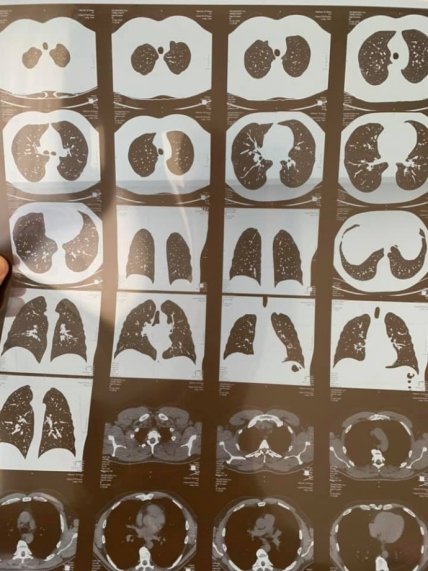

У народного депутата из группы "Довира" Сергея Вельможного обнаружилась двустороннее воспаление легких.

"К сожалению, мои друзья, это случилось. Прошел компьютерную томографию легких. Результат - двухсторонняя пневмония... Нет слов, я подавлен", - написал Вельможный в понедельник на своей странице в соцсети Facebook.